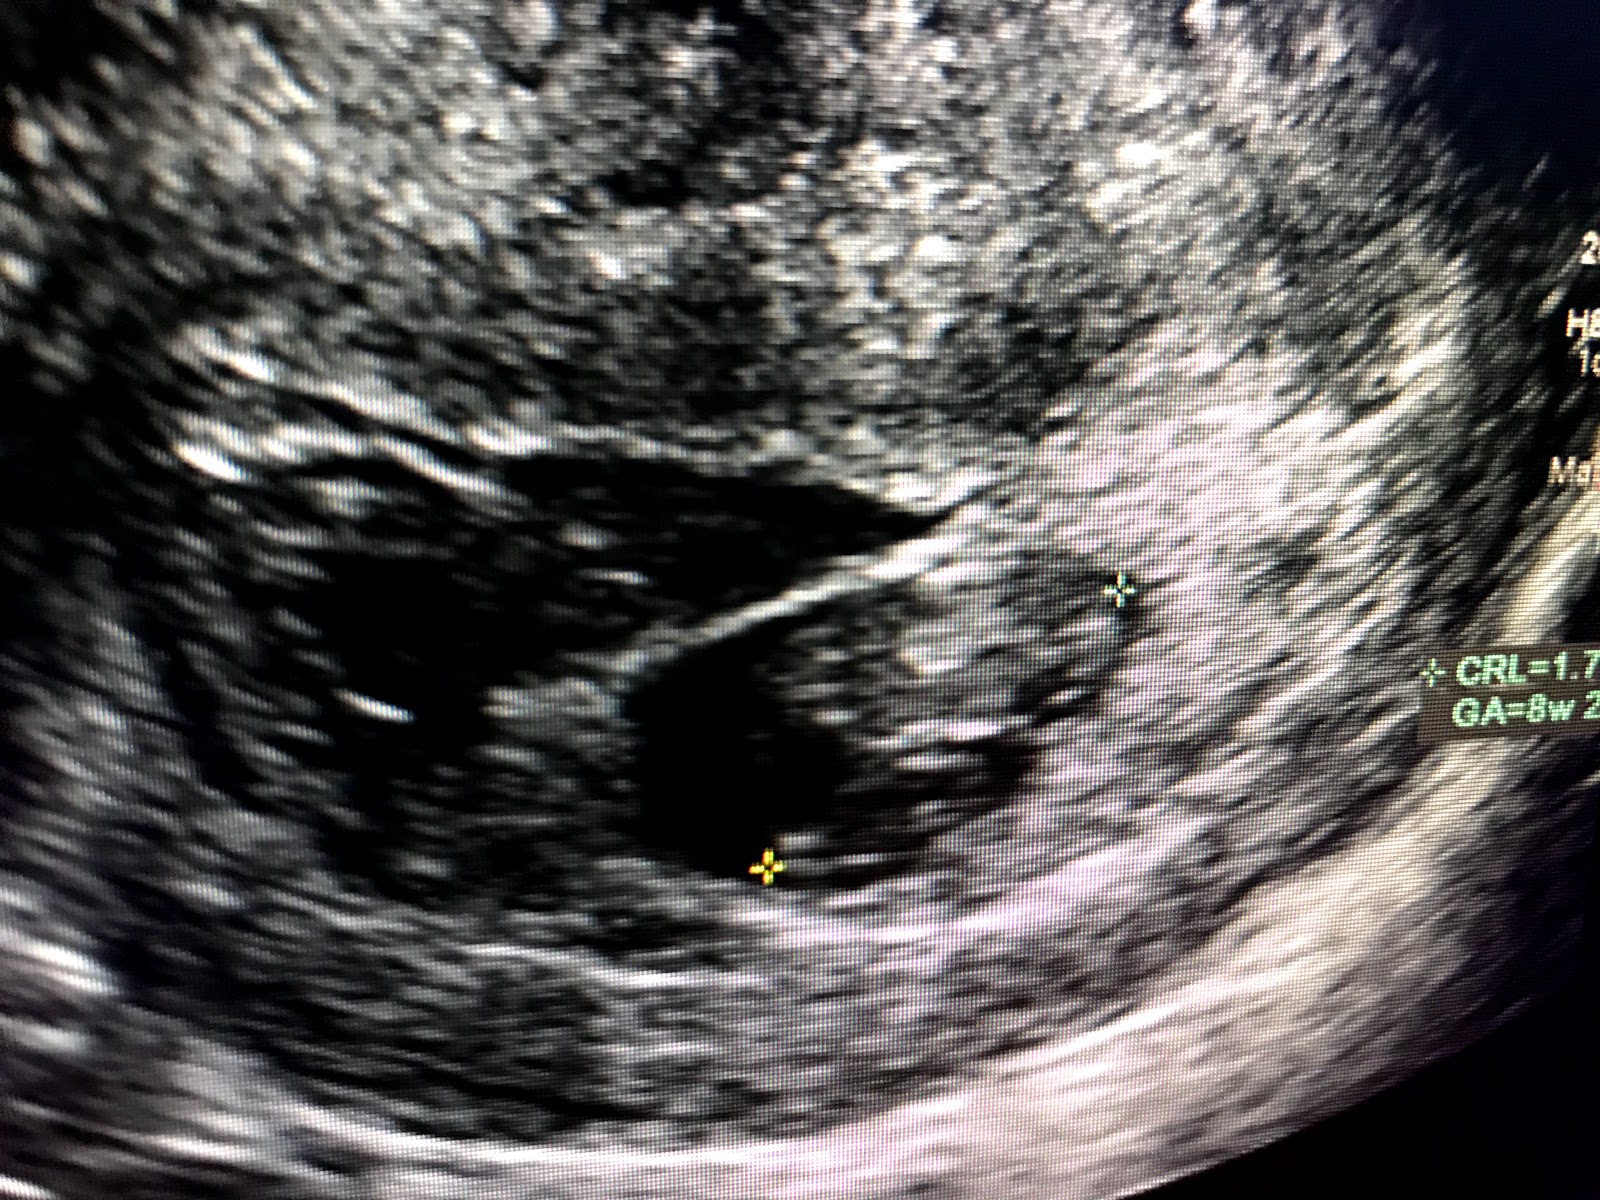

By 7:30 I had a positive test. The control line showed AFTER the test line. I knew I was overly pregnant by that point. So I took a moment, and cried. I cried out of nerves, scared-ness, and even sadness. I was terrified. I decided to go to the ER, since I received a positive and was still actively bleeding. Chad stayed home with the kids and I called my friend Shannon, who came and met me at the ER. After all the tests.. blood tests, ultrasound, and pap smear the doctor came in and confirmed that I was 8 weeks and 2 days pregnant. There was a strong heartbeat, butba large size subchorionic hemorrhage. A SCH, or subchorionic hemorrhage is the accretion of blood within the folds of the chorion which is the outer fetal membrane next to the placenta or between the uterus and the placenta itself.

Hello baby! Our 8week 2day old baby! The large black area that looks like another sack in the upper left was my subchorionic hemorrhage.

The doctor explained that we wouldn’t necessarily know the outcome of the pregnancy, but most go on to remain viable. Although, there is still risk of a miscarriage. So after a few hours in the ER I left with the restriction of pelvic rest, no heavy lifting, and to drink plenty of fluids and rest when I could.